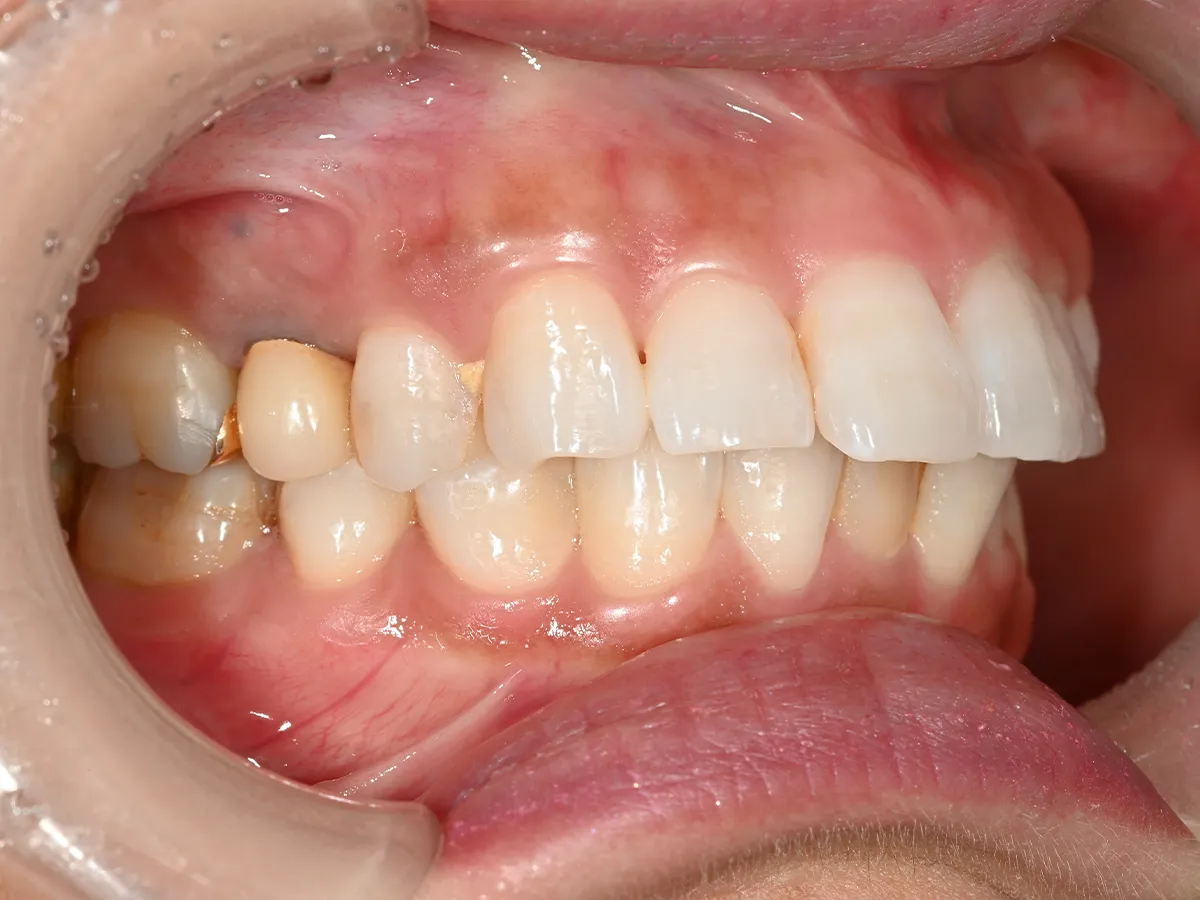

症例⑥

症例7_治療前 症例7_治療後

年齢・性別 26才・女性

治療方法 ブラケット矯正

治療期間 3年

治療総額 825,000円

特記事項 上顎4 4下顎55の4本抜歯